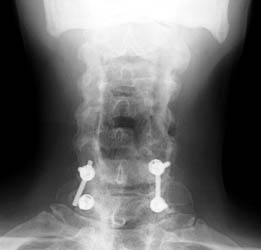

65 y.o male with prior surgery 23 years ago, secondary to trauma involving C4-5, C5-6 ACDF procedures. Now is 1 yr s/p bilateral C5 and C6 foraminotomy and C6-C7 posterior fusion and right iliac crest bone graft for persistent numbness and tingling for 2 years.

Radiographs obtained 5 months post-operatively demonstrate normal C6-7 fusion without evidence of hardware failure.